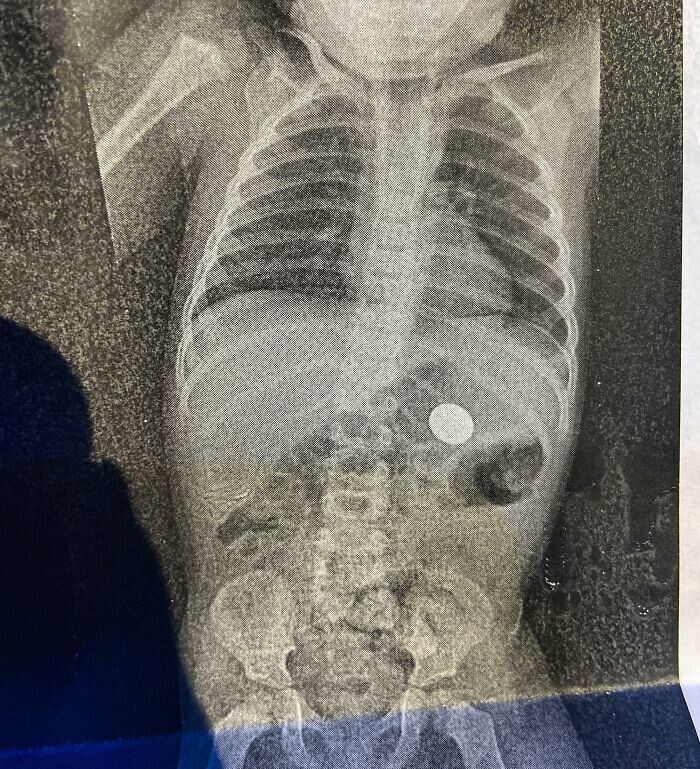

30. Вилучення гвинтів та пластин у День святого Валентина